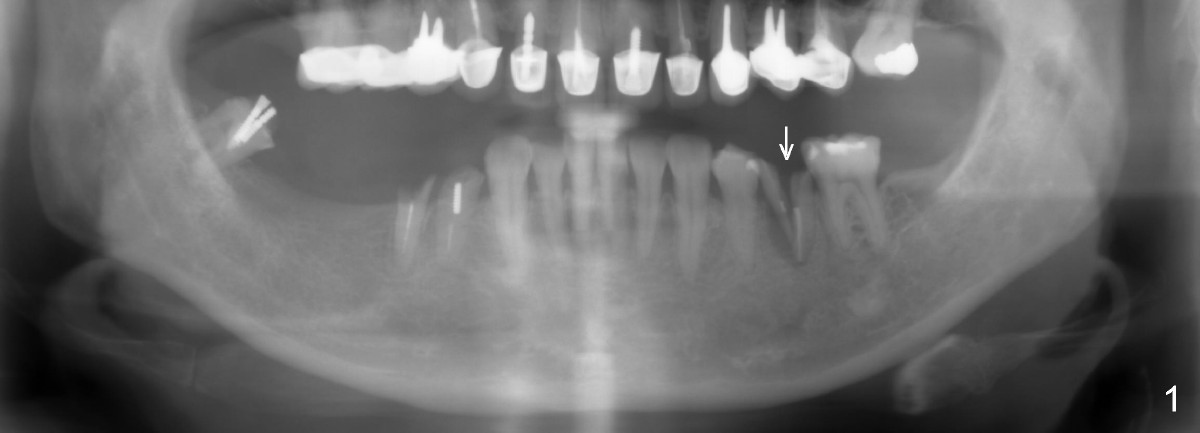

A 54-year-old lady has poor dentition. She seeks treatment because of pain associated with tooth fracture in the lower left 2nd premolar (Fig.1 arrow). The best option seems to be extraction and immediate implant. Thorough curettage after extraction is a key to get rid of infection.

Taking multiple intraop X-ray is also necessary for depth adjustment (Fig.3-5). For example, when a 5x20 mm tap is inserted at the depth of 17 mm, it is close to the mental loop (Fig.4), whereas the binding to the bone is minimal. So a larger implant is to be placed at a shallower depth (Fig.5: 6x17 mm with insertion torque >60 Ncm). The shallower implant placement creates limited space for future abutment and crown (Fig.6,7). A short abutment will be used and the implant margin will be prepared as low as possible. As expected, the wound heals in a week (Fig.8).